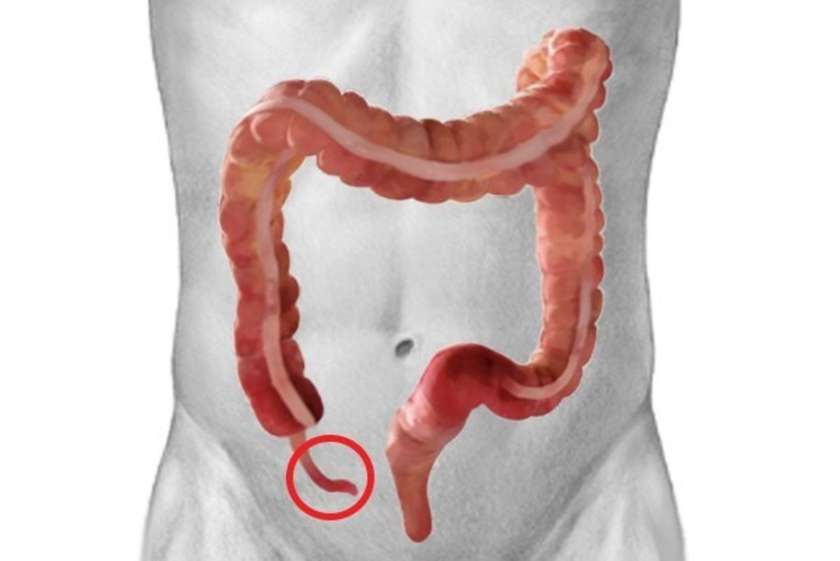

Ապենդիքս

Կույր աղիքի այս հատվածն օգնել է մեր նախնիներին մարսել կոշտ սնունդը: Սակայն այսօր մարդիկ դրա կարիքն այլևս չունեն: Հաճախ կլսեք, որ մարդիկ հեռացնում են կույր աղիքի այս ծայրային հատվածը: Նախկինում, երբ բժշկությունն այնքան էլ զարգացած չէր, ապենդիքսի պատճառով բազմաթիվ մարդիկ էին մահանում: